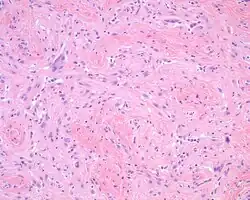

A high power hematoxylin and eosin stained slide showing the delicate neural tissue within dense fibrosis.

The overlying skin or squamous mucosa is intact and uninvolved by the process. There is normal glial tissue set within a fibrous connective tissue stroma. There is such blending, that the underlying process may be difficult to detect without special studies. In a few cases, large gemistocytes, neurons, choroid plexus, ependyma, and retinal pigmented cells may be seen.[2][3]